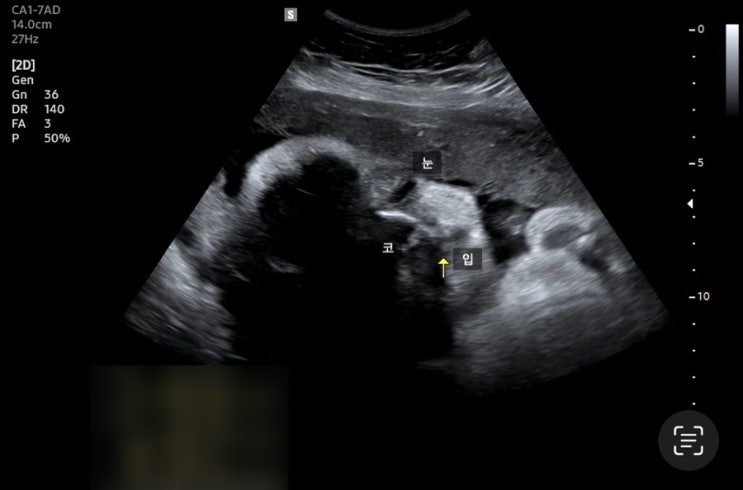

[임신 38주차] 증상, 드디어 엘디 육아 하루 전♥️

나는 38주 5일에 제왕절개를 예약했다:) 오늘은 38주 4일! 첨으로 예약 포스팅이 아니네?! 그리고 마지막 ...

[임신 37주차] 증상, 줄어든 양수량, 제왕절개 수술 동의서 작성, 제대혈 고민!

?37주차 증상? 1) 양수검사 늘 넘쳐나던 양수가 줄어들엇다고 하셨다!!! 네?!!!! 안암고대병원에서도...